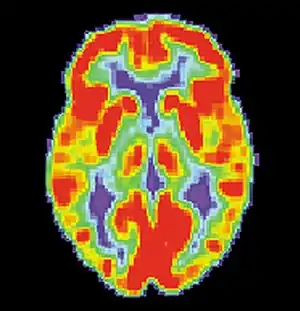

It is evident that long-term cocaine abuse alters brain structures. Research has shown that the brain structures that are immediately affected by long-term cocaine abuse include: cerebral hypoperfusion in the frontal, periventricular and temporal-parietal.[77] These structures play a role in various memory systems. Furthermore, the drug cocaine elicits its desirable effects by blocking the DRD1 dopamine receptors in the striatum, resulting in increased dopamine levels in the brain.[77] These receptors are important for the consolidation of procedural memory. These increased dopamine levels in the brain resultant of cocaine use is similar to the increased dopamine levels in the brain found in schizophrenics.[78] Studies have compared the common memory deficits caused by both cases to further understand the neural networks of procedural memory. To learn more about the effects of dopamine and its role in schizophrenia see: dopamine hypothesis of schizophrenia. Studies using rats have shown that when rats are administered trace amounts of cocaine, their procedural memory systems are negatively impacted. Specifically, the rats are unable to effectively consolidate motor-skill learning.[79] With cocaine abuse being associated with poor procedural learning, research has shown that abstinence from cocaine is associated with sustained improvement of motor-skill learning (Wilfred et al.).